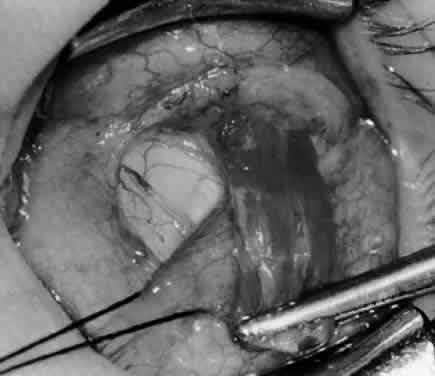

Fig. 9. A Westcott scissor is used to dissect the intermuscular septum and expose the insertion of the inferior oblique muscle.

Fig. 10. The inferior oblique muscle is placed on the Green muscle hook. The exposed insertion is ready for myotomy, myectomy, disinsertion, placement of sutures for recession, or removal for the extirpation procedure.

Fig. 11. Sutures are placed into the insertion of the inferior oblique muscle before it is sectioned from the globe for the recession procedure.

Fig. 12. An Aebli scissor is placed beneath the inferior oblique muscle insertion before it is sectioned from the globe.